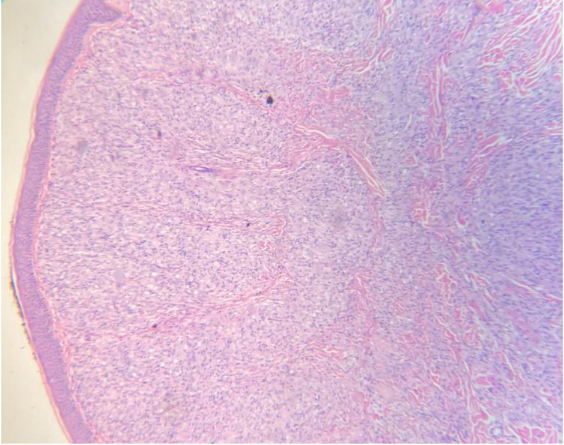

Pemeriksaan Histopatologi (Biopsi Kulit): Pertimbangkan untuk melakukan biopsi kulit, terutama jika diagnosis klinis dan bakteriologis tidak memberikan hasil yang jelas atau jika terdapat presentasi kasus yang atipikal . Pada pemeriksaan histopatologi, cari adanya sel-sel histiosit berbentuk spindel yang tersusun dalam pola storiform serta adanya Grenz zone, yang merupakan ciri khas dari Kusta Histoid . Pada kasus Kusta Relaps, gambaran histopatologi mungkin menunjukkan infiltrat granulomatosa, peningkatan IB dibandingkan dengan hasil sebelumnya, dan potensi adanya infiltrat limfositik di sekitar saraf atau granuloma berbusa .

Gambar 2. Pada biopsy tampak infiltrasi difus oleh histiosit. Grenz zone terdapat diantara epidermis dan infiltrate

Dari sudut pandang histopatologi, Kusta Histoid memiliki ciri khas berupa adanya sel-sel histiosit berbentuk spindel yang tersusun dalam pola pusaran atau storiform di dermis . Selain itu, sering ditemukan adanya Grenz zone, yaitu band acellular di bawah epidermis yang memisahkan infiltrat seluler dari epidermis .